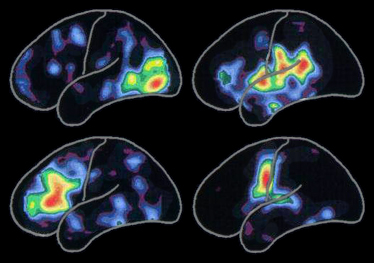

La scansione PET (positron emission tomography, tomografia ad emissione di positroni) riportata a sinistra mostra i tipici schemi dell'attività cerebrale associata a:

L'attività è più intensa nelle aree rosse e diminuisce negli altri colori dell'arcobaleno dal giallo al blu-violetto.